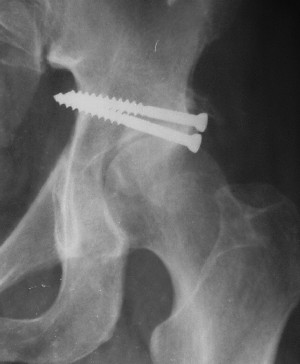

При поступлении в госпиталь 3.06.03

Больной 18 мая 2003 года в автоаварии получил перелом левой вертлужной впадины, вывих бедра. Госпитализирован в один из стационаров области.Вывих вправлен. В последствии бедро вывихивалось еще дважды. На консультацию был представлен снимок от 19.05.03г., больной переведен к нам 3.06.03г. Снимок при поступлении - перелом впадины, задне-верхний вывих бедра. 05.06.2003 г. выполнено открытое вправление вывиха левого бедра и остеосинтез стенки вертлужной впадины двумя винтами. Послеоперационный период без осложнений. Объем движений в левом тазобедренном суставе восстановился полностью. Выписан на амбулаторное лечение в удовлетворительном состоянии с рекомендациями 3 месяца ходить на костылях без нагрузки на оперированную конечность. На контрольных рентгенограммах левого тазобедренного сустава 13.10.2003 г. - признаки консолидации перелома; плотность, форма головки и состояние суставных поверхностей удовлетворительные. Разрешена дозированная осевая нагрузка, на конечность с использованием дополнительной опоры. 19.12.2003 г. больной обратился с жалобами на боли в левом тазобедренном суставе. На рентгенограммах левого тазобедренного сустава 19.12.2003 г., 20.02.04г. - асептичекий некроз головки бедра. 5.04.04г. - эндопротез. Сейчас ходит без трости, не хромает. Особенность эндопротезирования - при удалении винтов прослежена линия перелома заднего края впадины и предложено установить чашку несколько меньшего диаметра, чтобы она была покрыта несломанной частью.